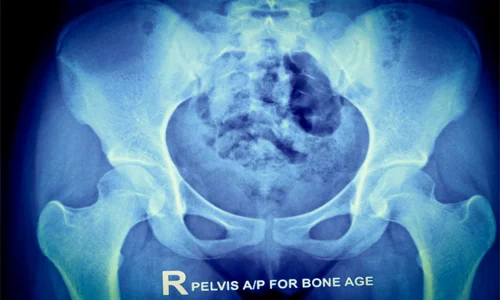

موفقیت درمان دررفتگی تکاملی مفصل لگن (DDH) در کودکان ۶ تا ۱۸ ماهه، تنها با جااندازی اولیه حاصل نمی‌شود، بلکه نیازمند پیگیری منظم و طولانی‌مدت است که می‌تواند تا پایان دوره رشد کودک ادامه یابد. ابزار اصلی این نظارت، رادیوگرافی (عکسبرداری با اشعه ایکس) است.

این تصاویر به متخصص ارتوپد کودکان امکان می‌دهد تا بر رشد حفره لگنی (استابولوم) نظارت کند و مطمئن شود که به اندازه کافی عمیق شده و پوشش لازم برای سر استخوان ران (فمور) را فراهم می‌کند. همچنین رادیوگرافی برای بررسی دقیق موقعیت و شکل سر فمور و پیشگیری از عوارض جدی مانند ایسکمی آواسکولار (مرگ بافت استخوانی به دلیل اختلال خونرسانی) حیاتی است. این پیگیری‌های منظم امکان تشخیص زودهنگام هرگونه عود، بدشکلی یا نارسایی رشدی استابولوم را فراهم می‌سازد تا در صورت لزوم مداخله جراحی اصلاحی در مناسب‌ترین زمان انجام شده و نتیجه درمانی بلند مدت تضمین شود.